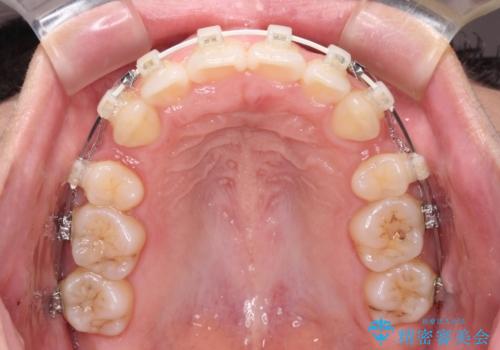

- 矯正装置

- 審美装置

- 1年8ヶ月

- 前歯の出っ歯と口元の閉じにくさを気にして来院された患者様です。

口元を積極的に引っ込めるために、上下左右の小臼歯4本を抜歯することとしました。